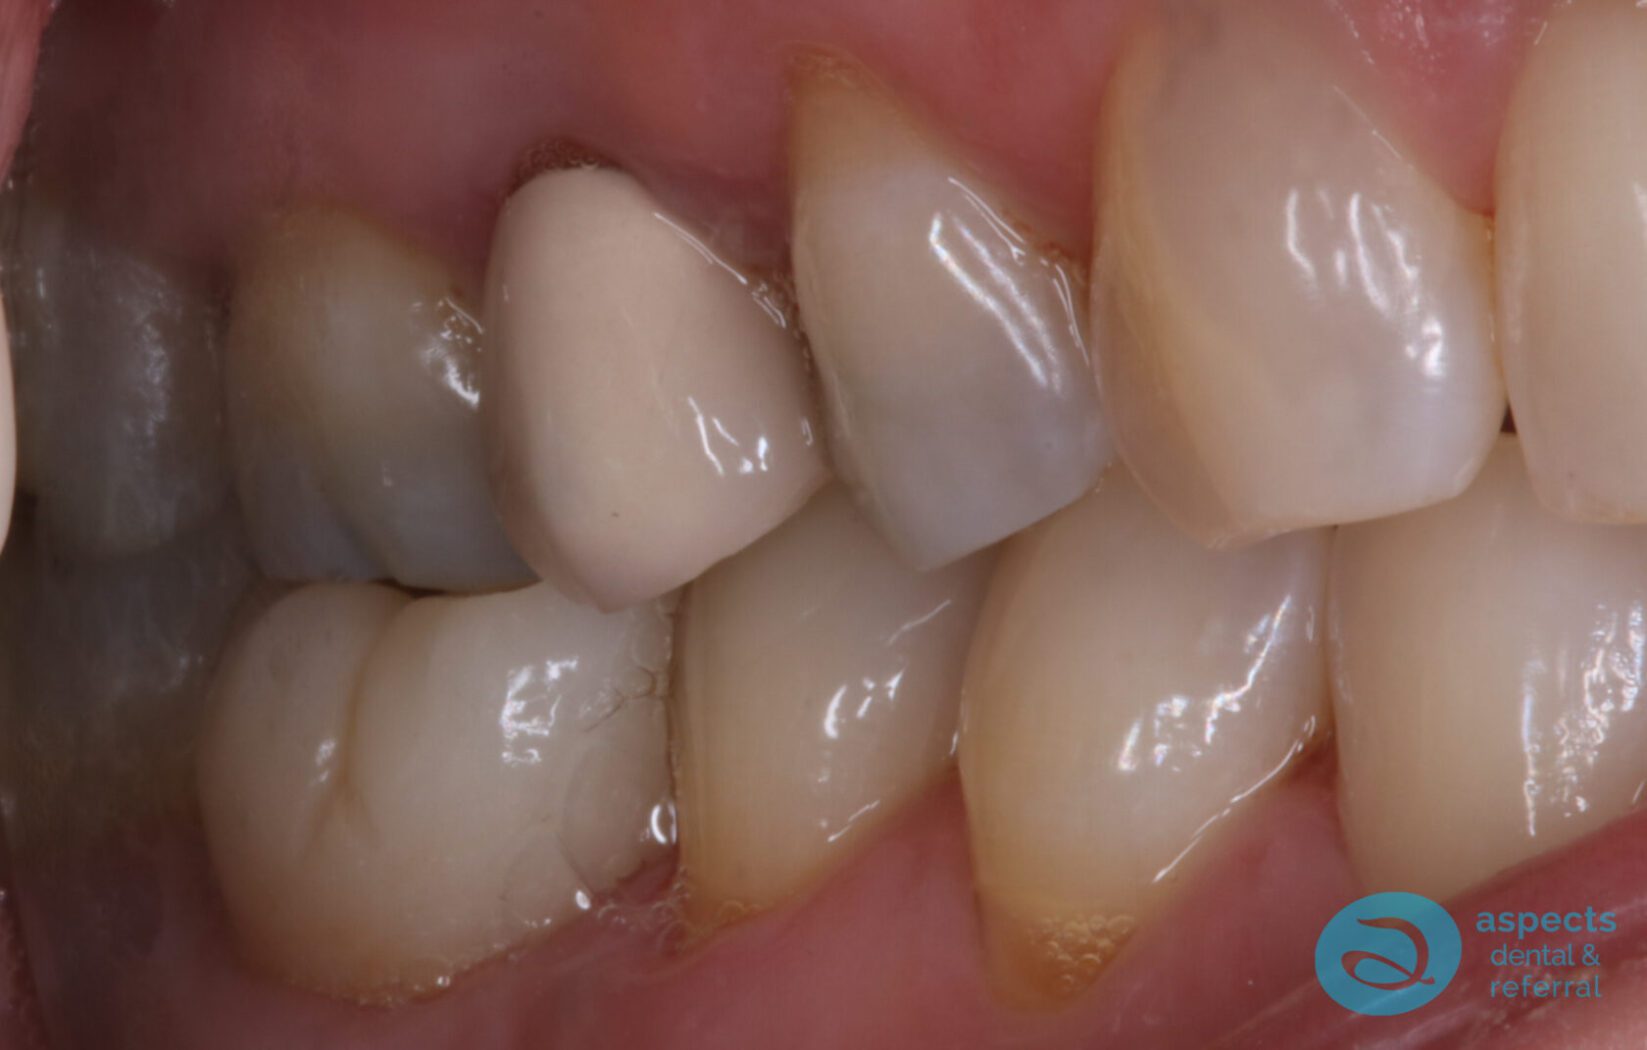

After a 12-week healing period, a Dental Implant was successfully placed at the extraction site. Following adequate osseointegration and soft tissue healing, the implant was restored with an all-ceramic zirconia crown, achieving both functional stability and aesthetic restoration.

After Dental Implant Photo